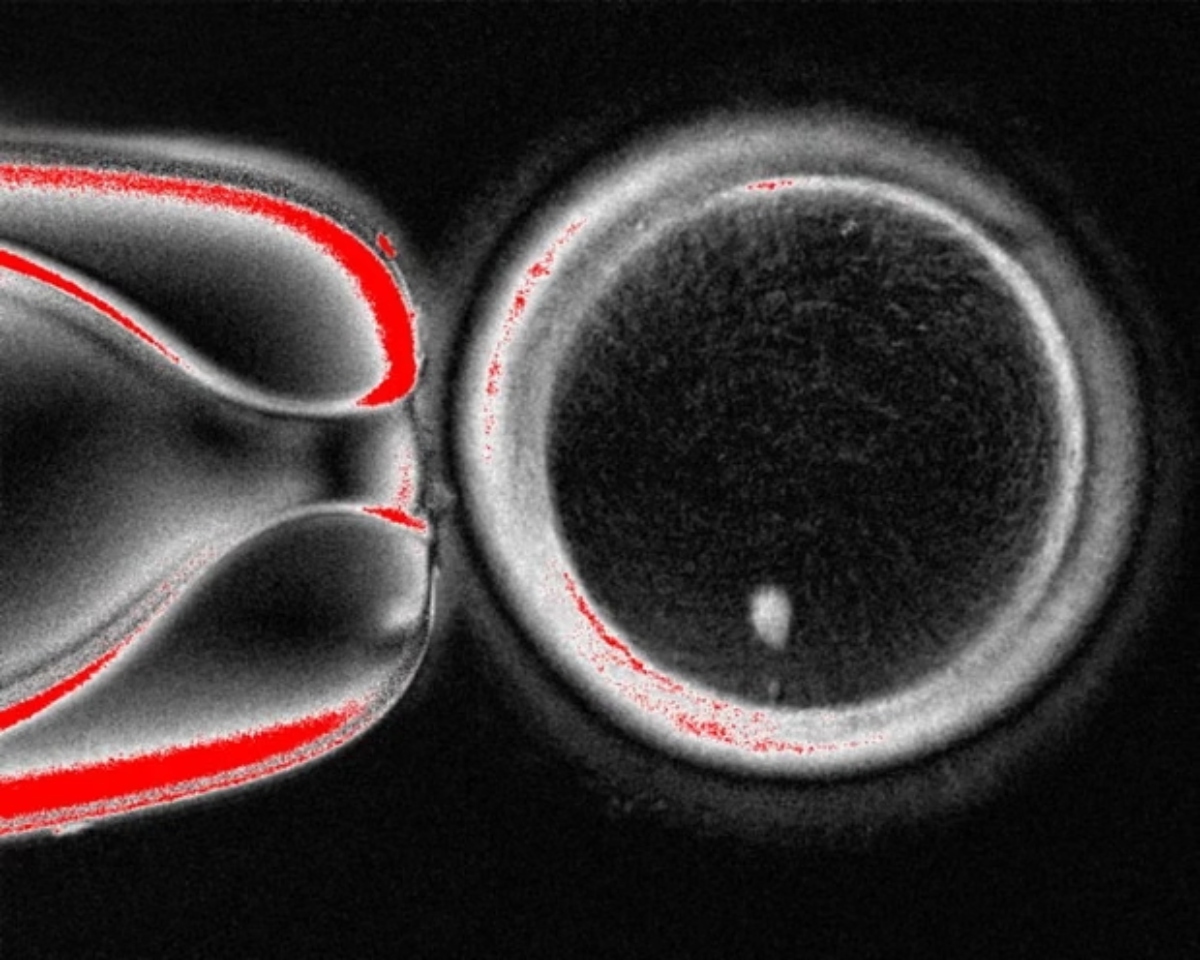

Η ομάδα του Όρεγκον ακολούθησε παρόμοια προσέγγιση, συλλέγοντας δερματικά κύτταρα από γυναίκες και αφαιρώντας τον πυρήνα από κάθε κύτταρο. Ο πυρήνας περιέχει τα 46 χρωμοσώματα που φέρουν περίπου 20.000 γονίδια που αποτελούν τον ανθρώπινο γενετικό κώδικα. Κάθε πυρήνας δερματικού κυττάρου τοποθετήθηκε σε ένα υγιές ωάριο δότη, του οποίου ο δικός του πυρήνας είχε αφαιρεθεί.

Σε άρθρο της που δημοσιεύθηκε στο επιστημονικό περιοδικό Nature Communications, η ερευνητική ομάδα περιγράφει πώς ξεπέρασε το πρόβλημα των χρωμοσωμάτων. Μετά τη γονιμοποίηση των ωαρίων με σπέρμα, τα ενεργοποίησαν χρησιμοποιώντας μια ένωση που ονομάζεται ροσκοβιτίνη. Αυτό είχε ως αποτέλεσμα τα ωάρια να μεταφέρουν περίπου τα μισά από τα χρωμοσώματά τους σε μια δομή που ονομάζεται πολικό σωμάτιο, αφήνοντας τα υπόλοιπα χρωμοσώματα να ζευγαρώσουν με αυτά του σπέρματος.

Σε ένα υγιές γονιμοποιημένο ανθρώπινο ωάριο, τα 23 χρωμοσώματα της μητέρας συνδυάζονται με τα 23 του πατέρα. Ωστόσο, η ομάδα διαπίστωσε ότι τα χρωμοσώματα στα ωάριά τους διαχωρίζονταν και συνδυάζονταν τυχαία. Αυτό οδήγησε σε έμβρυα πρώιμου σταδίου με λανθασμένο αριθμό χρωμοσωμάτων και λανθασμένους συνδυασμούς χρωμοσωμάτων.

Από τα 82 ωάρια που δημιουργήθηκαν στο εργαστήριο του Όρεγκον, λιγότερα από 10% αναπτύχθηκαν στο στάδιο όπου τα έμβρυα εξωσωματικής γονιμοποίησης μεταφέρονται συνήθως στη μήτρα, γεγονός που υποδηλώνει ότι η διαδικασία δεν είναι ιδιαίτερα αποτελεσματική. Κανένα από αυτά δεν καλλιεργήθηκε πέραν των έξι ημερών.